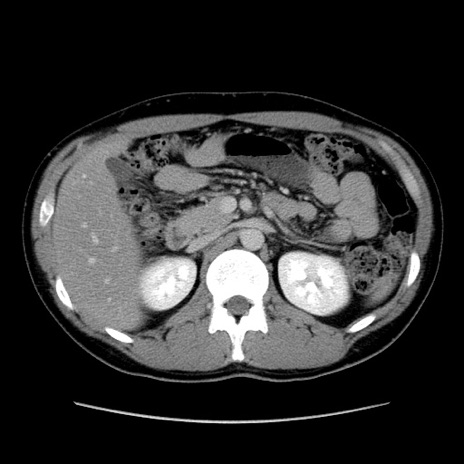

症例36(横断像)

【症例】20歳代 男性

【主訴】心窩部痛

【現病歴】今朝より上腹部痛あり。一旦軽快していたが再度出現したため救急要請。昨日夕に白身の魚を含む刺身を食べた。

【身体所見】BP 136/89mmHg、HR 74/min、BT 37.0℃、腹部:膨満、軟、心窩部に圧痛あり。反跳痛なし、筋性防御なし、腸雑音やや亢進あり。

【データ】WBC 17700、CRP 0.48